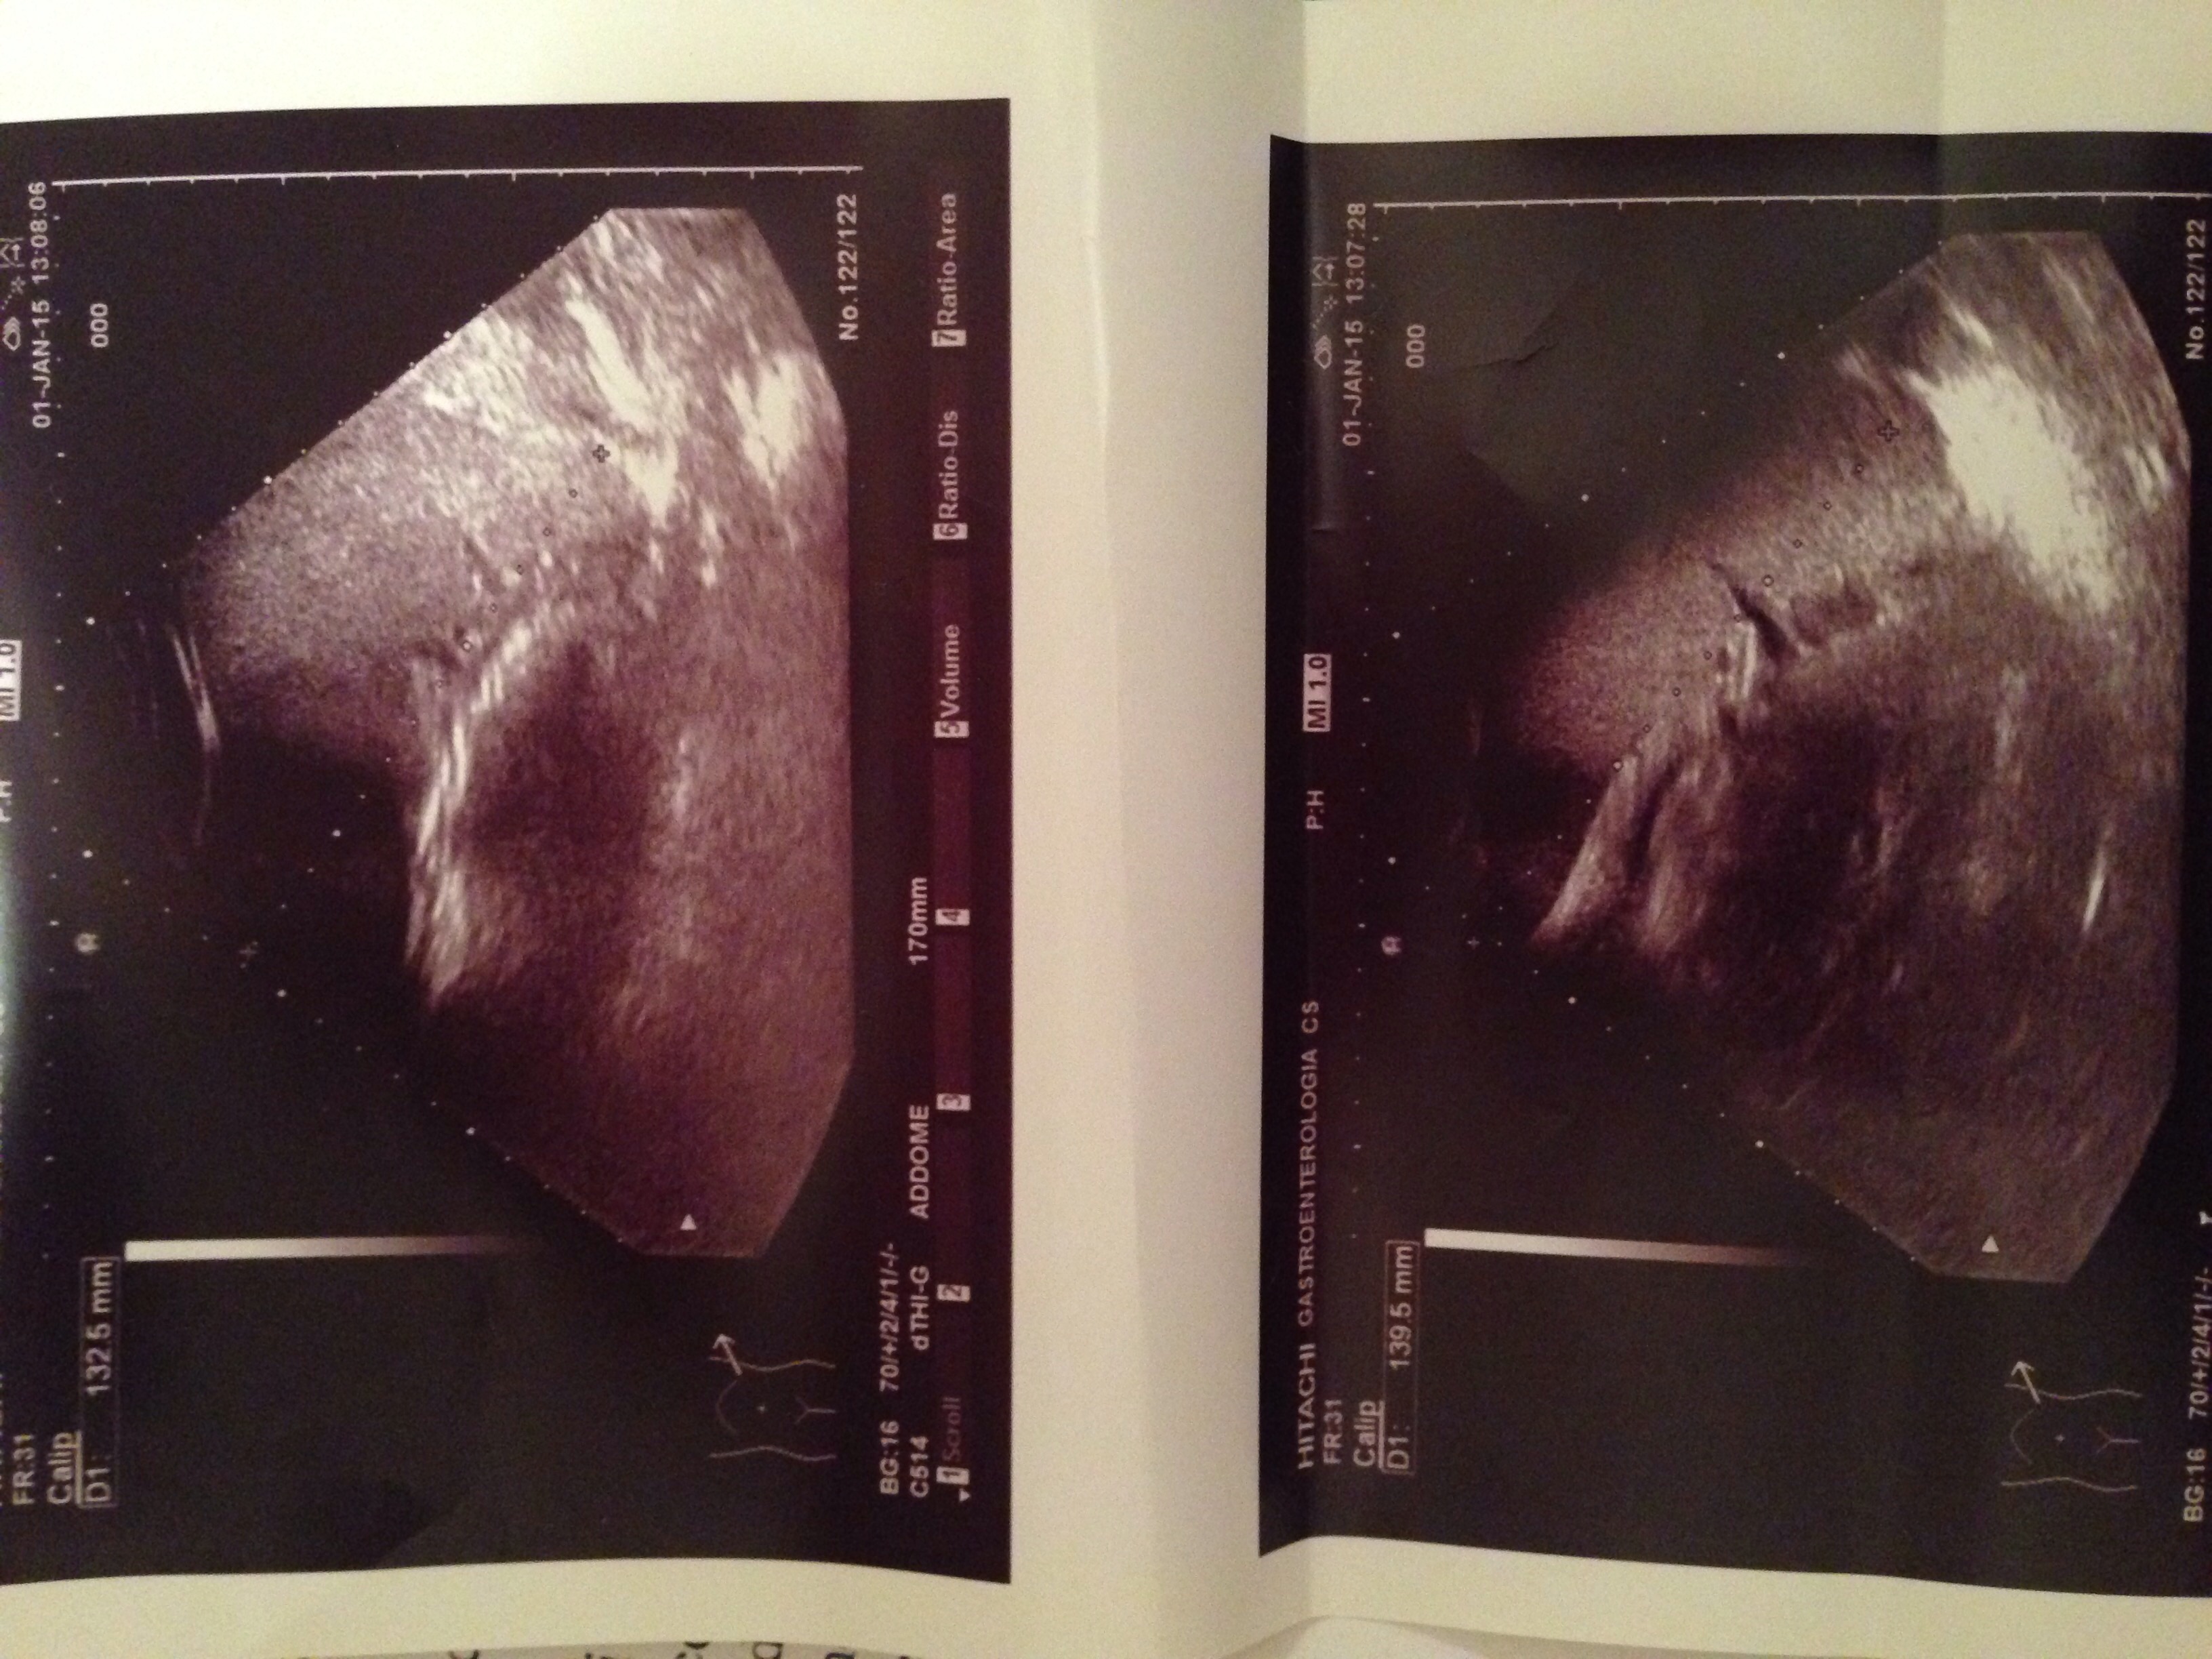

Oggi 1 gennaio 2015 riporta i seguenti valori

D1:132.5 mm

D1:139.5 mm

*Lateralemente (TRACE ) c'è scritto credo significa lateramente quando mi sono girato per prendere le rispettive misure

C1 40.46 cm (Callip)

AI 55.11 cm2